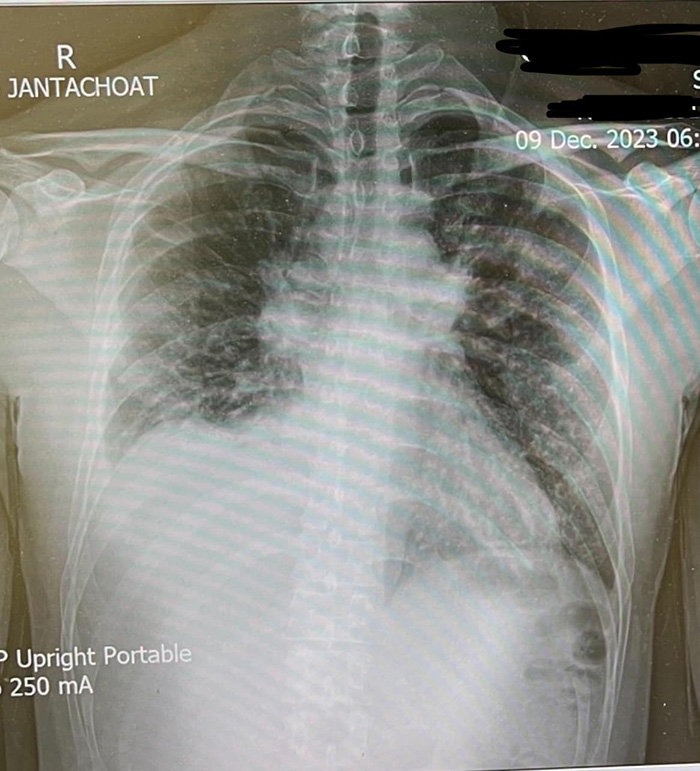

สารวัตรรุ่งคุณได้ไปที่ห้องฉุกเฉิน และผลจากซีทีสแกนก็พบว่าขั้วปอดขยาย มีน้ำในเยื่อหุ้มหัวใจ ต่อมน้ำเหลืองที่ขั้วปอดโตขึ้น ปอดอาจจะมีการติดเชื้อ ปอดข้างขวามีก้อนขึ้นมาขนาด 1.6 ซม. มีน้ำในปอดเยอะ กระดูกหน้าอกเริ่มมีการกระจายตัวของเชื้อ จนต้องเจาะน้ำในปอดออกไปตรวจ